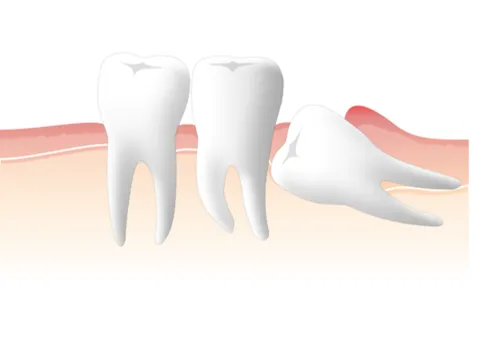

親知らずはまっすぐに生えることが少なく、横向きに生えてきたり、歯ぐきが腫れて痛みが出たりして、トラブルを起こすことが多々あります。また、一番奥にあって歯磨きしにくく、虫歯や歯周病になるリスクも高いため、レントゲンやCTで撮影し、口腔内のチェックを行った上で早めの抜歯をおすすめしています。

歯が硬く成長しきる前の柔らかい状態で行うため、比較的スムーズに行えるケースがあります。親知らずは、生える方向や位置によっては隣の歯を押したり、歯並びに影響を及ぼす場合があります。発育途中の段階で歯胚を除去しておくことで、そうした将来的なトラブルを事前に防ぐことにつながります。